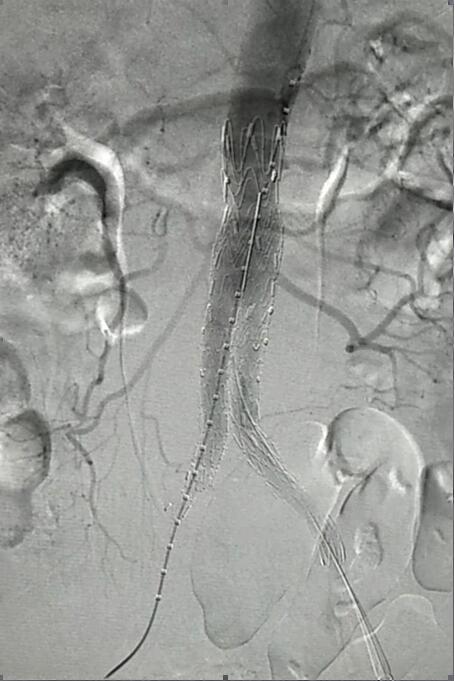

血管介入科行腹主動(dòng)脈瘤覆膜支架隔絕術(shù)(“褲衩”支架植入)。圖2